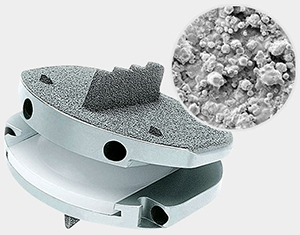

The prodisc L implant has been designed to maintain the physiological range of motion in the spine. The implant was developed using the clinically proven ball and socket concept used in joint replacement implants for over 40 years. The prodisc L implant is composed of three components – two cobalt chrome alloy (CoCrMo) endplates and an ultra-high molecular weight polyethylene (UHMWPE) inlay.

Secure Fixation

- Patented central keel and lateral spikes provide secure primary fixation

- Plasma-sprayed titanium surface on bone contacting surfaces promotes integration